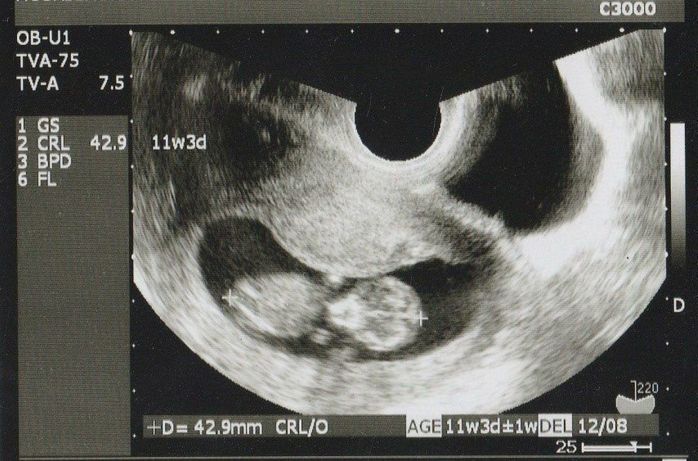

妊娠11週目のエコー写真

この頃になると、はっきりと頭部と体・二つの手も写っています。「とても赤ちゃんらしくなったね」と、夫とワクワクしていたのを覚えています。こんなにちゃんと人間らしい形になっているのに、まだ4cmちょっとしかない我が子が、すでに愛おしくてたまりませんでした。